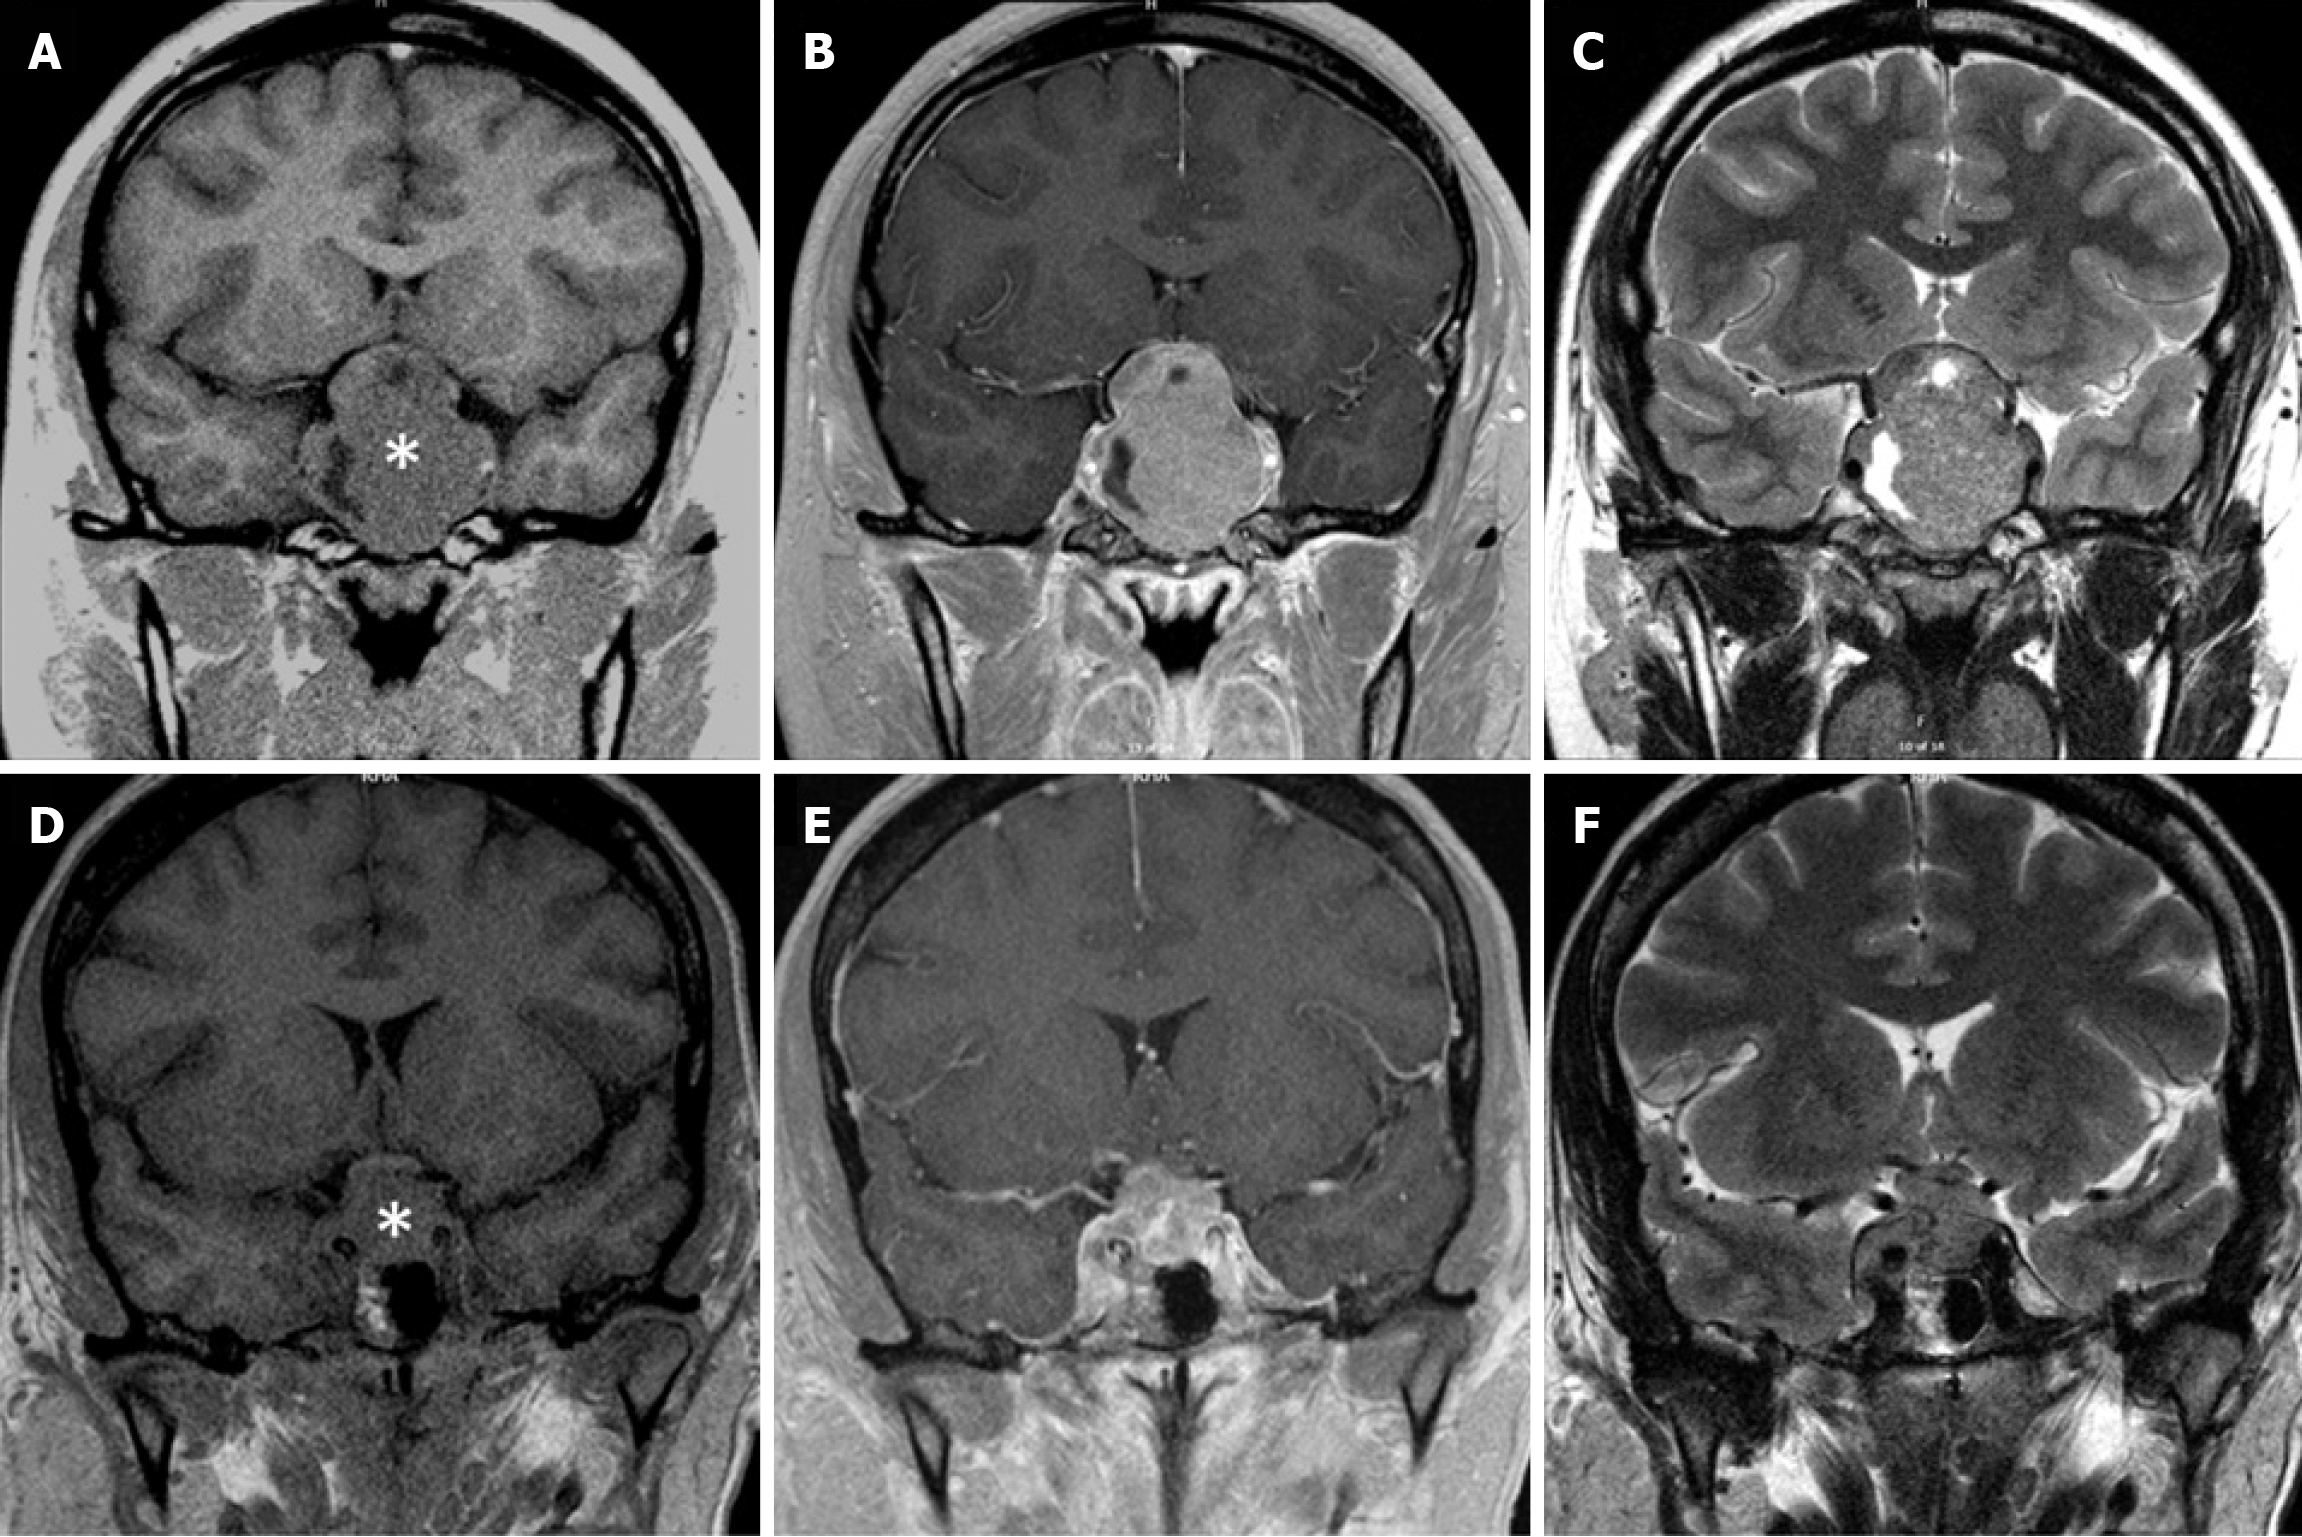

Figure 2 Magnetic resonance imaging of pituitary macroadenoma and sellar atypical teratoid/rhabdoid tumor.

A-C: A 4.1 cm × 4.4 cm macroprolactinoma of a 19-year-old male; D-F: A 2.2 cm × 1.8-cm sellar atypical teratoid/rhabdoid tumor of a 45-year-old female. T1 imaging without contrast (A and D). T1 imaging after contrast administration (B and E). T2 imaging (C and F). Asterisk, sellar mass. Note the limited cavernous sinus invasion despite large tumor size and the optic chiasm thinning in the patient with macroprolactinoma. Also note the extensive bilateral cavernous sinus invasion but intact optic chiasm in the patient with sellar atypical teratoid/rhabdoid tumor. Panel E is reproduced from Yu[17]. Citation: Yu R. Sellar Mass in 2 Patients With Acute-Onset Headache and Visual Symptoms: Not Your Usual Pituitary Adenoma. AACE Clin Case Rep 2023; 9: 197-200. Copyright © 2015 Elsevier Inc. Published by Elsevier Inc. This is an open access article with User License: Creative Commons Attribution-NonCommercial-NoDerivs (CC BY-NC-ND 4.0). See: https://creativecommons.org/licenses/by-nc-nd/4.0/.